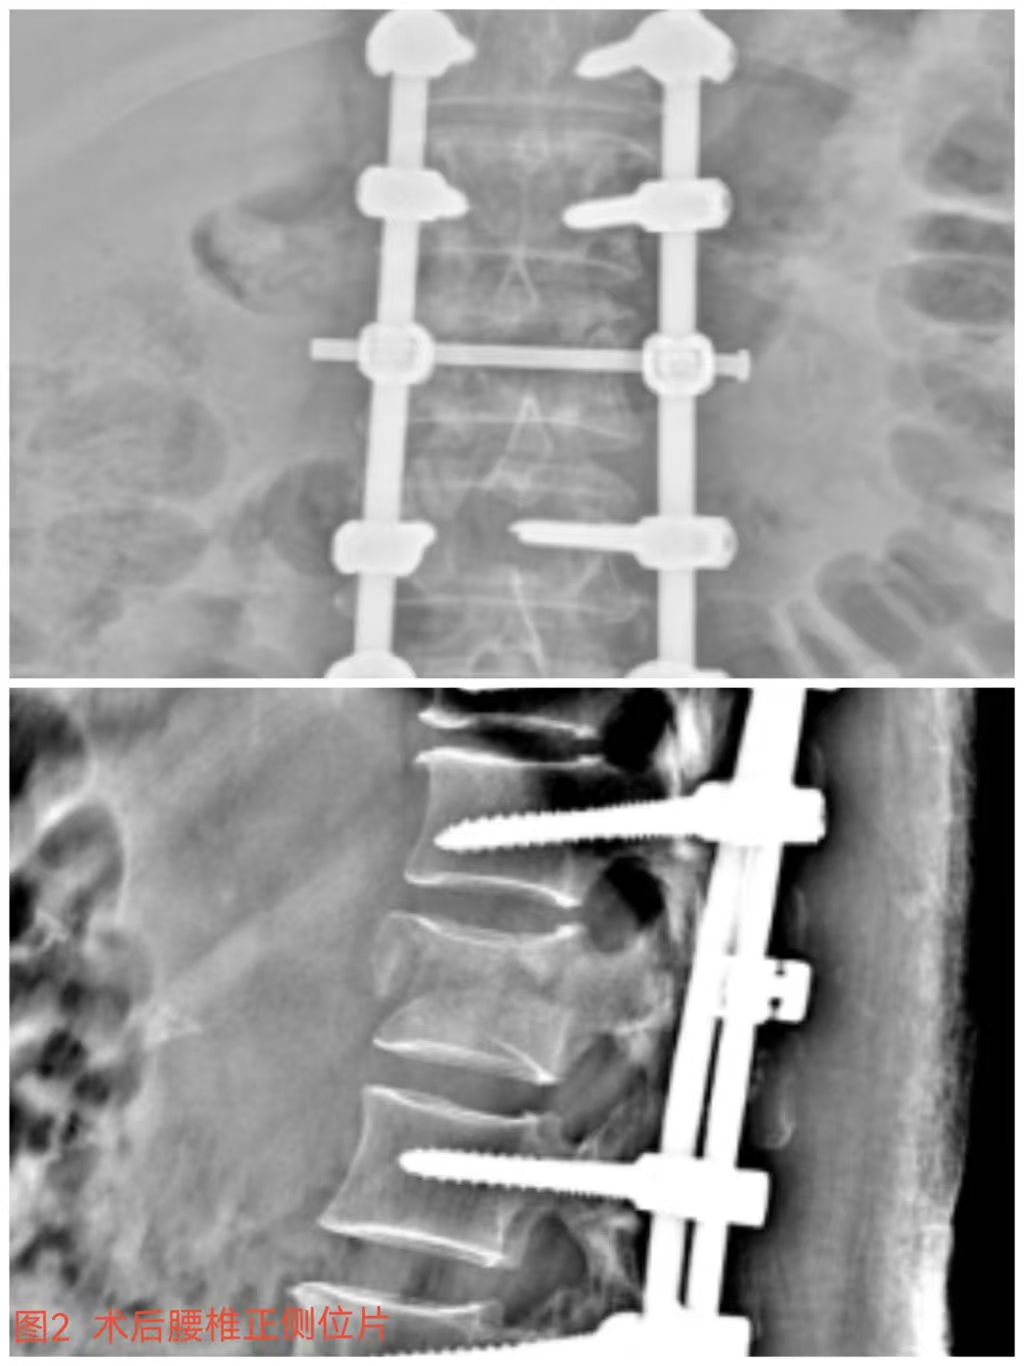

入院時(shí)患者躺在床上不能動(dòng)彈,眼神中透漏著深深的無助,對(duì)于她來說這種傷情無疑是沉重的,尤其是腹股溝以下感覺消失、雙下肢肌力0級(jí),這意味著其下肢無法活動(dòng)及站立,仿佛被命運(yùn)按下了暫停鍵;與病人及家屬充分溝通病情后,第一時(shí)間給予對(duì)癥治療,監(jiān)測(cè)患者生命體征,行腰椎核磁檢查(圖1)提示:腰1椎體爆裂性骨折,椎體后緣塌陷致骨性椎管狹窄,壓迫脊髓神經(jīng),結(jié)合患者病情及輔助檢查可診斷為:“L1椎體爆裂性骨折伴雙下肢截癱”。